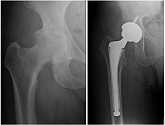

Еndoprosthesis of hip joint

In the late stages of arthrosis of the hip joint, medial fractures of the femoral neck in the older age group, the only way to recover is to replace the affected joint with an artificial joint - arthroplasty.

This method allows you to return the limb's limb, the full volume of movements in the affected joint, to save from constant pain and crunch during movements and, as a consequence, to return the patient to a full active life.

Below are presented X-ray photographs and photographs, illustrating the amount of motion in the affected joint before and after surgery.